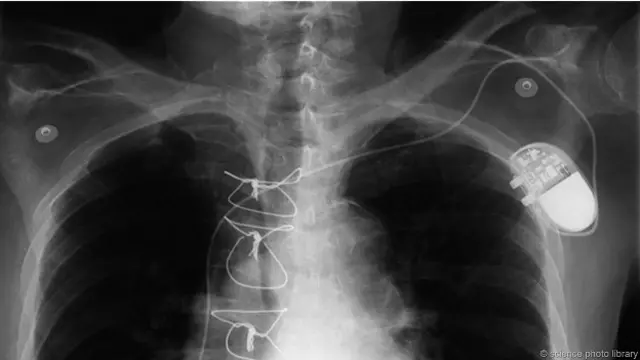

От сердца к сердцу

Кардиостимуляторы и ИКД, напротив, чаще всего извлекаются из тела владельца после его смерти. Перед кремацией их извлекают практически всегда, поскольку батареи могут взорваться при высокой температуре нагрева. То же самое касается нейростимуляторов спинного мозга и некоторых типов имплантируемых насосов для дозирования лекарств, поскольку конструкция тех и других содержит электронные компоненты.

Автор фото, Science Photo Library

После извлечения имплантаты, как правило, уничтожаются. В Европейском союзе, США и других странах существуют правила, запрещающие повторное использование имплантируемых медицинских устройств. Вместе с тем, нарастает тенденция извлекать эти приборы для повторного использования в развивающемся мире.

При цене в 4 тыс. долларов за кардиостимулятор и 20 тыс. за ИКД бывшие в употреблении имплантаты – единственная возможность для миллионов людей воспользоваться оборудованием, способным спасти им жизнь. В Соединенном Королевстве благотворительная организация Pace4Life забирает действующие кардиостимуляторы в похоронных бюро - для последующего использования в Индии. Аналогичным образом поступают в США.

Журнал Annals of Internal Medicine недавно обнародовал результаты американской программы, получившей название "Проект "Мое сердце – твое сердце". Оказалось, что среди 75 пациентов, получивших бывшие в употреблении ИКД, не было зафиксировано ни одного случая инфекции или отказа приборов. Организация подала в федеральное агентство США по надзору за качеством продуктов и медикаментов запрос на получение разрешения отправлять за рубеж переработанные устройства для стимуляции сердца.